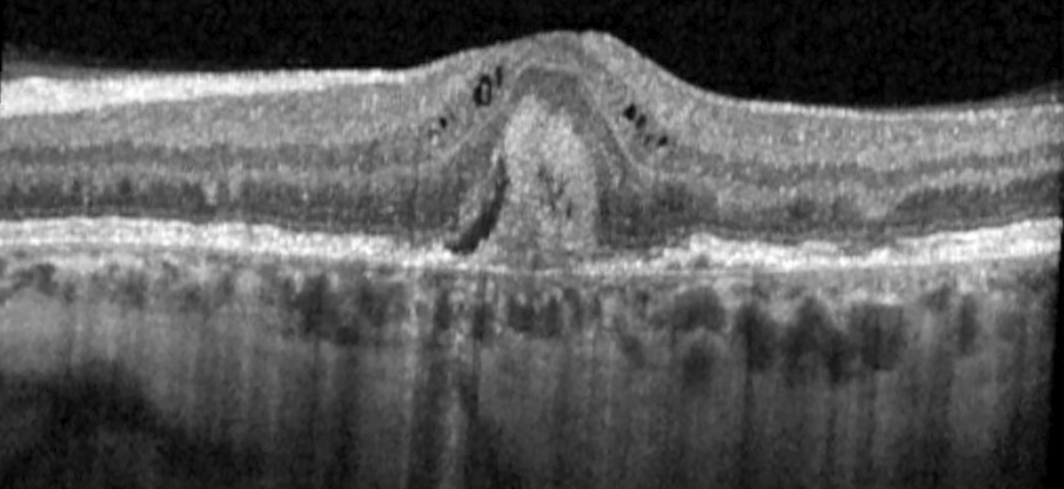

A 55‐year‐old woman in the United States, with a history of interstitial cystitis diagnosed at age 33 years, was referred for pattern macular dystrophy. Her primary complaint was difficulty reading, despite using bifocals. Her medications included hydroxyzine, amitriptyline and pentosan polysulfate (PPS). She had taken 300 mg of PPS daily for 21 years (cumulative dose, 2.3 kg). Visual acuity with correction was 6/7.5 and intraocular pressure was normal in both eyes. Fundus examination revealed bilateral perifoveal pigmentary deposits without haemorrhage or exudate. Spectral domain optical coherence tomography (SD‐OCT; SPECTRALIS HRA + OCT, Heidelberg Engineering), demonstrated irregular retinal pigment epithelium and small pigment epithelial detachments in the maculae of both eyes without cystoid macular oedema. Near‐infrared reflectance imaging and autofluorescence showed hyper‐reflective patches and speckled areas of hypo‐ and hyper‐autofluorescence, respectively, in each eye (Box 1). Fluorescein angiogram demonstrated retinal pigment epithelial staining without leakage. Cessation of PPS and routine monitoring were recommended. Subsequently, the patient developed unilateral choroidal neovascularisation of the left eye (Box 2), which was treated with an intravitreal antivascular endothelial growth factor agent.

Fundus findings in PPM include parafoveal pigmentary deposits, macular vitelliform deposits, and paracentral retinal pigment epithelium atrophy. Short wavelength fundus autofluorescence imaging typically demonstrates an irregular pattern of hyper‐ and hypo‐autofluorescence in the macula. Near‐infrared reflectance imaging may reveal irregular hyper‐reflective spots in the macula. SD‐OCT may show nodular excrescences at the level of the retinal pigment epithelium, outer retinal tubulations, and patchy loss of the retinal pigment epithelium. These findings may mimic those of other diseases, such as age‐related macular degeneration.

Box 1 – Multimodal retinal imaging of the right and left maculae in a patient with retinopathy associated with pentosan polysuflate intake

(A) Colour fundus photos showing the perifoveal pigmentary deposits (arrows); (B) autofluorescence fundus photos highlighting macular speckled hyper‐ and hypo‐autofluorescence (arrows); (C) near‐infrared reflectance photos demonstrating hyper‐reflective deposits (arrows); (D) optical coherence tomography highlighting irregularity of the retinal pigment epithelium with small pigment epithelial detachments (arrows).